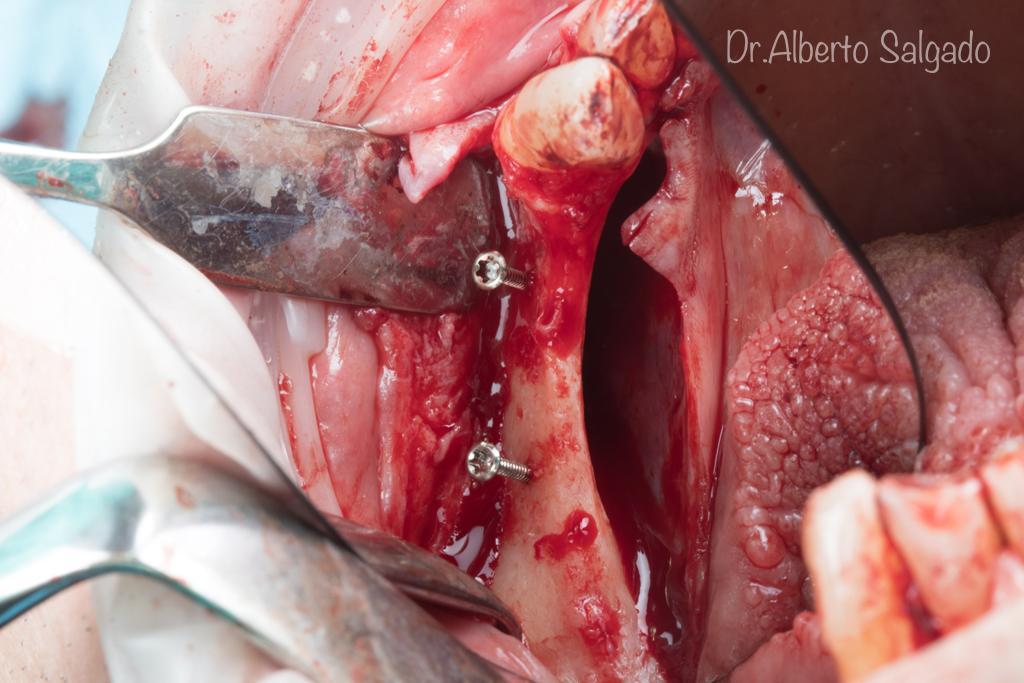

Dr. Alberto

Salgado